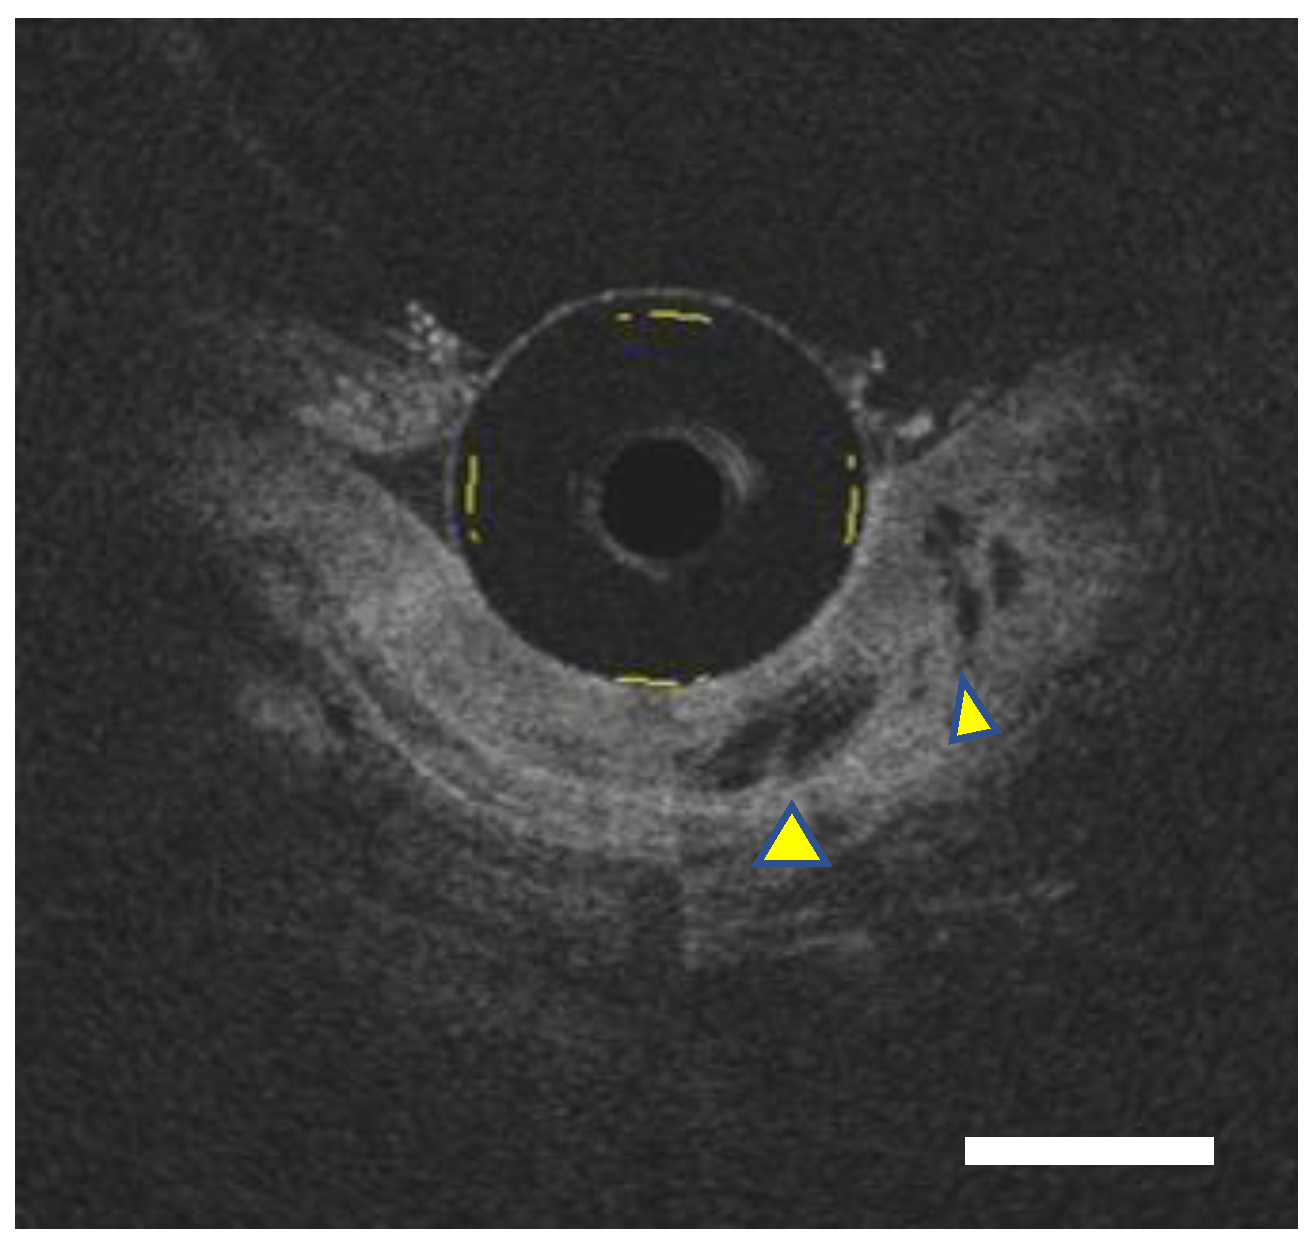

- Hatta, W.; Uno, K.; Koike, T.; Ara, N.; Asano, N.; Iijima, K.; Imatani, A.; Fujishima, F.; Shimosegawa, T. Feasibility of optical coherence tomography for the evaluation of Barrett’s mucosa buried underneath esophageal squamous epithelium. Dig. Endosc. 2015, 28, 427–433. [Google Scholar] [CrossRef] [PubMed]

- Yun, S.H.; Tearney, G.J.; Vakoc, B.J.; Shishkov, M.; Oh, W.Y.; Desjardins, A.E.; Suter, M.J.; Chan, R.C.; Evans, J.A.; Jang, I.-K.; et al. Comprehensive volumetric optical microscopy in vivo. Nat. Med. 2006, 12, 1429–1433. [Google Scholar] [CrossRef] [PubMed]

- Swager, A.; Boerwinkel, D.F.; de Bruin, D.M.; Weusten, B.L.; Faber, D.J.; Meijer, S.L.; van Leeuwen, T.G.; Curvers, W.L.; Bergman, J.J. Volumetric laser endomicroscopy in Barrett’s esophagus: A feasibility study on histological correlation. Dis. Esophagus 2016, 29, 505–512. [Google Scholar] [CrossRef] [PubMed]

- Swager, A.-F.; Tearney, G.J.; Leggett, C.L.; van Oijen, M.G.; Meijer, S.L.; Weusten, B.L.; Curvers, W.L.; Bergman, J.J. Identification of volumetric laser endomicroscopy features predictive for early neoplasia in Barrett’s esophagus using high-quality histological correlation. Gastrointest. Endosc. 2017, 85, 918–926.e7. [Google Scholar] [CrossRef]

- Alshelleh, M.; Inamdar, S.; McKinley, M.; Stewart, M.; Novak, J.S.; Greenberg, R.E.; Sultan, K.; Devito, B.; Cheung, M.; Cerulli, M.A.; et al. Incremental yield of dysplasia detection in Barrett’s esophagus using volumetric laser endomicroscopy with and without laser marking compared with a standardized random biopsy protocol. Gastrointest. Endosc. 2018, 88, 35–42. [Google Scholar] [CrossRef] [PubMed]

- Struyvenberg, M.R.; De Groof, A.J.; Kahn, A.; Weusten, B.L.A.M.; Fleischer, D.E.; Ganguly, E.K.; A. Konda, V.J.; Lightdale, C.J.; Pleskow, D.K.; Sethi, A.; et al. Multicenter study on the diagnostic performance of multiframe volumetric laser endomicroscopy targets for Barrett’s esophagus neoplasia with histopathology correlation. Dis. Esophagus 2020, 33, doaa062. [Google Scholar] [CrossRef] [PubMed]